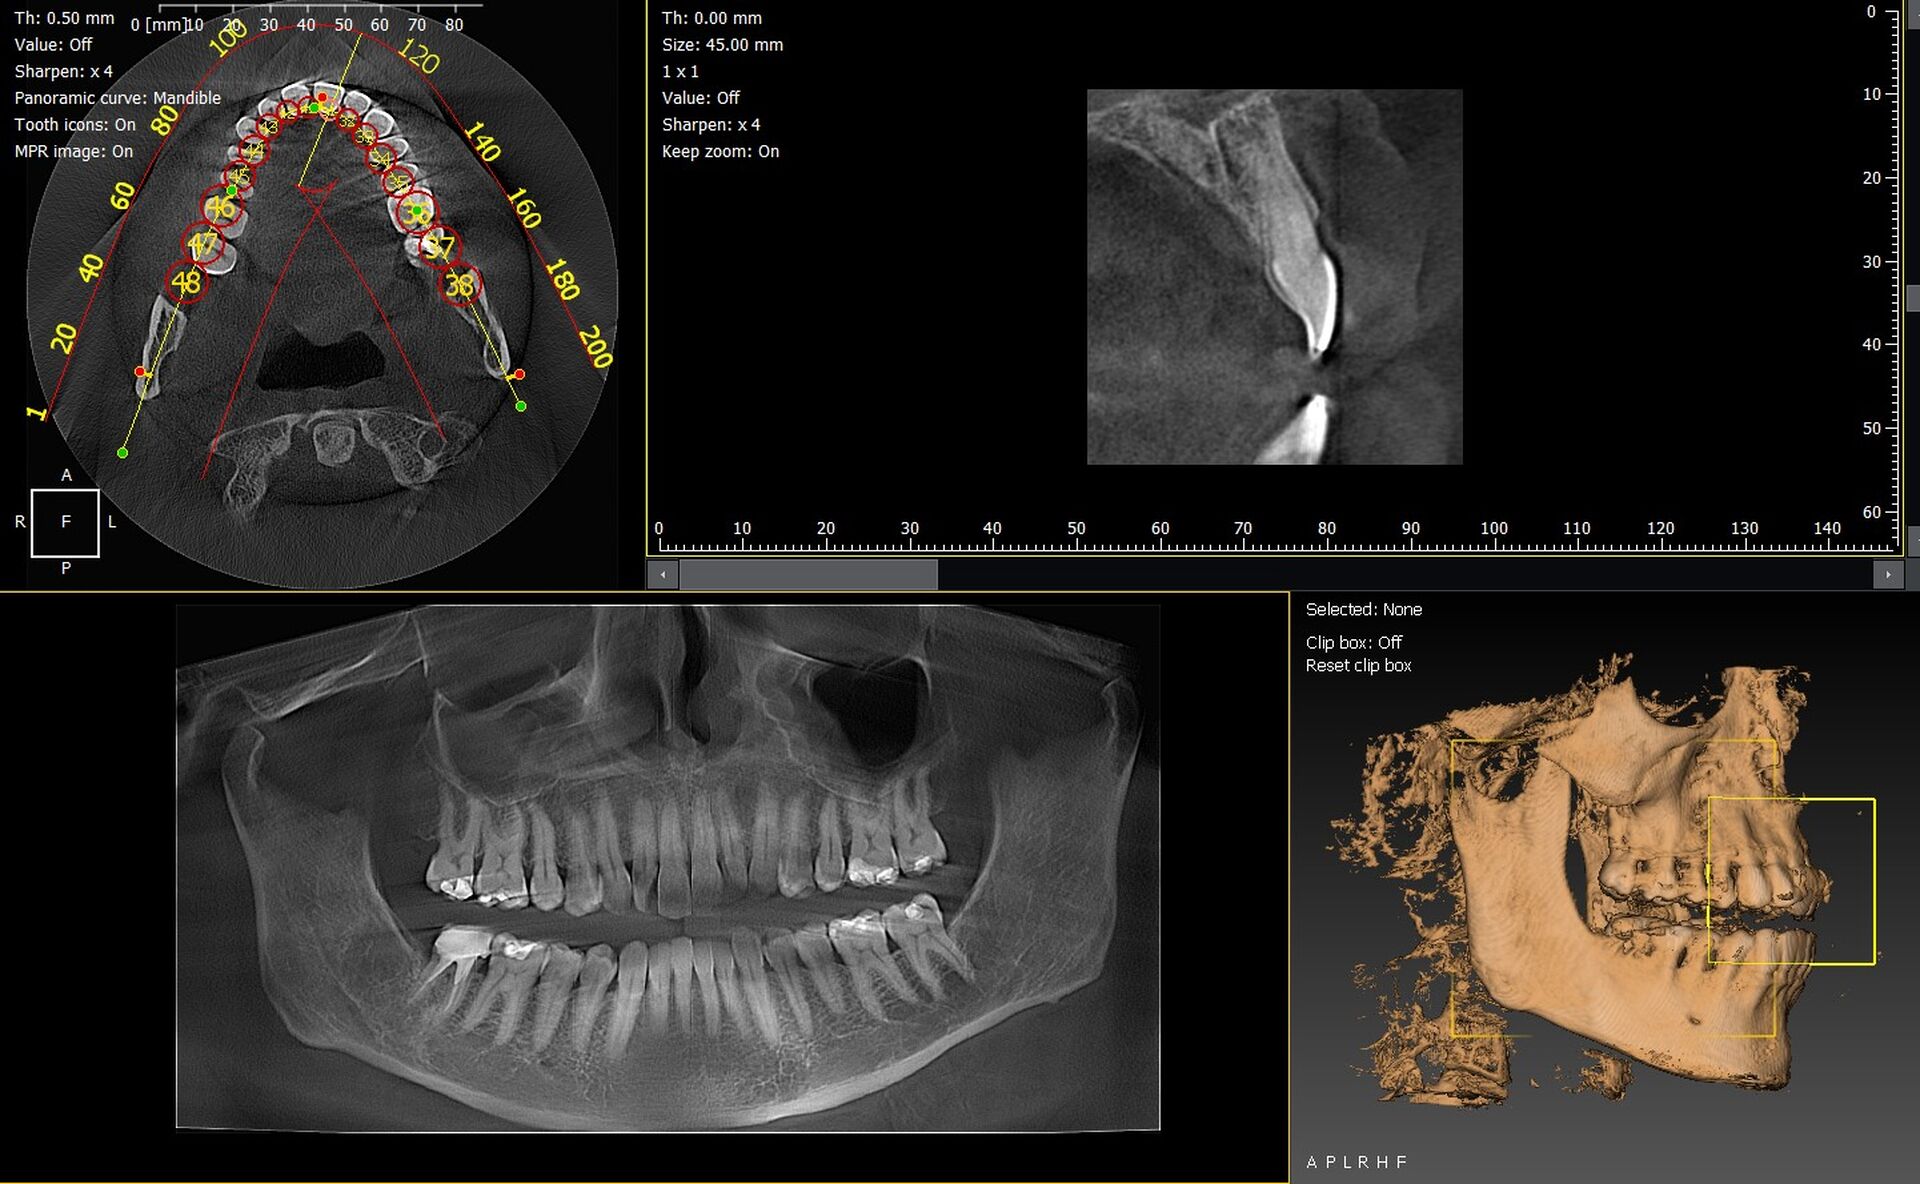

Les cabinets dentaires de Cagnes-sur-Mer et du département des Alpes-Maritimes (06) cherchent de plus en plus à moderniser leur plateau technique grâce à des solutions d’imagerie 3D performantes. Parmi les équipements les plus fiables du marché, les panoramiques CBCT 3D VistaVox de Dürr Dental et l’Owandy I-Max 3D se démarquent par leur précision, leur ergonomie et leur compatibilité avec les logiciels métiers.

VistaVox : la précision 3D signée Dürr Dental

Le VistaVox 3D offre un volume d’imagerie parfaitement adapté à l’arcade dentaire, ce qui permet :

• une visualisation nette des structures anatomiques,

• une analyse fiable en implantologie, endodontie et chirurgie orale,

• une réduction de dose grâce à un champ d’exploration optimisé,

• un positionnement simplifié du patient.

Owandy I-Max : compact, moderne et polyvalent

L’I-Max 3D séduit par son format mural ultra-compact, idéal pour les cabinets de ville. Ses atouts :

• support 2D, 3D et céphalométrie selon les options,

• excellente qualité d’image en haute résolution.

• des images 3D d’une grande précision,

• des diagnostics plus fiables,